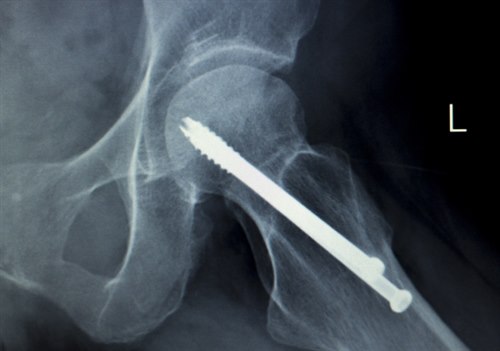

Brudd stabilisert med skruer. Illustrasjonsbilde: Colourbox.comFormålet med behandlingen er å få satt bruddet på plass og festet det slik at det er stabilt. Dette reduserer også smerten. Til dette kreves operasjon. Det ideelle tidspunktet for en slik operasjon er innen 24 timer etter uhellet.

Total hofteprotese. Røntgenbilde: Colourbox.comVed brudd uten feilstilling er det enighet om at behandlingen skal være skruer eller nagler uansett alder. For brudd med feilstilling, derimot, anbefales ulike former for kirurgi basert på alder, bruddtype og andre forhold. For noen er det best å sette inn en halvprotese (bare leddhodet skiftes), men for andre er det bedre å sette inn en totalprotese (skifter både leddhode og leddskål).

Unge, friske pasienter under 60-65 år bør behandles med skrue og/eller nagler (osteosyntese) uavhengig av grad av feilstilling.